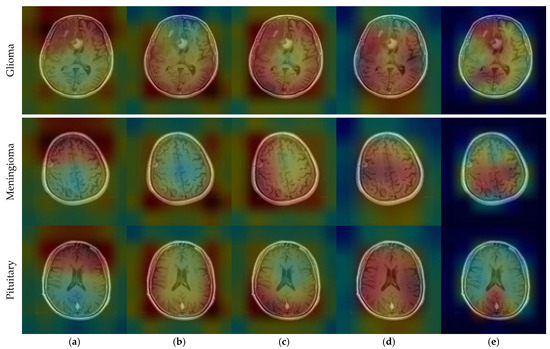

CNN outputs visualized on a heat map with Grad-CAM for Dataset 1, Dataset 2, and Dataset 3 are represented in Figure 10, Figure 11 and Figure 12, respectively. The original images are overlaid with a color spectrum ranging from blue to red, where the red regions indicate the dominant focus during model predictions. The sample images in Figure 1 were used as the original images in the Grad-CAM application. Grad-CAM analyses of the models in the ensemble framework are presented for three data sets. Figure 10 shows that while all models focus on the brain, different models may focus on different regions of the same MRI image. This trend also helps to increase feature diversity. This can be considered an indicator of better performance with ensemble learning.

Figure 10.

CNN outputs visualized on a heat map with Grad-CAM for Dataset 1: (a) DenseNet121, (b) DenseNet201, (c) EfficientNetV2S, (d) ResNet50, and (e) ResNet101.

Figure 11.

CNN outputs visualized on a heat map with Grad-CAM for Dataset 2: (a) DenseNet121, (b) DenseNet169, (c) DenseNet201, (d) InceptionResNetV2, and (e) ResNetRS100.

Figure 12.

CNN outputs visualized on a heat map with Grad-CAM for Dataset 3: (a) DenseNet201; (b) InceptionResNetV2; (c) MobileNetV2; (d) RegNetX008; (e) ResNet101.